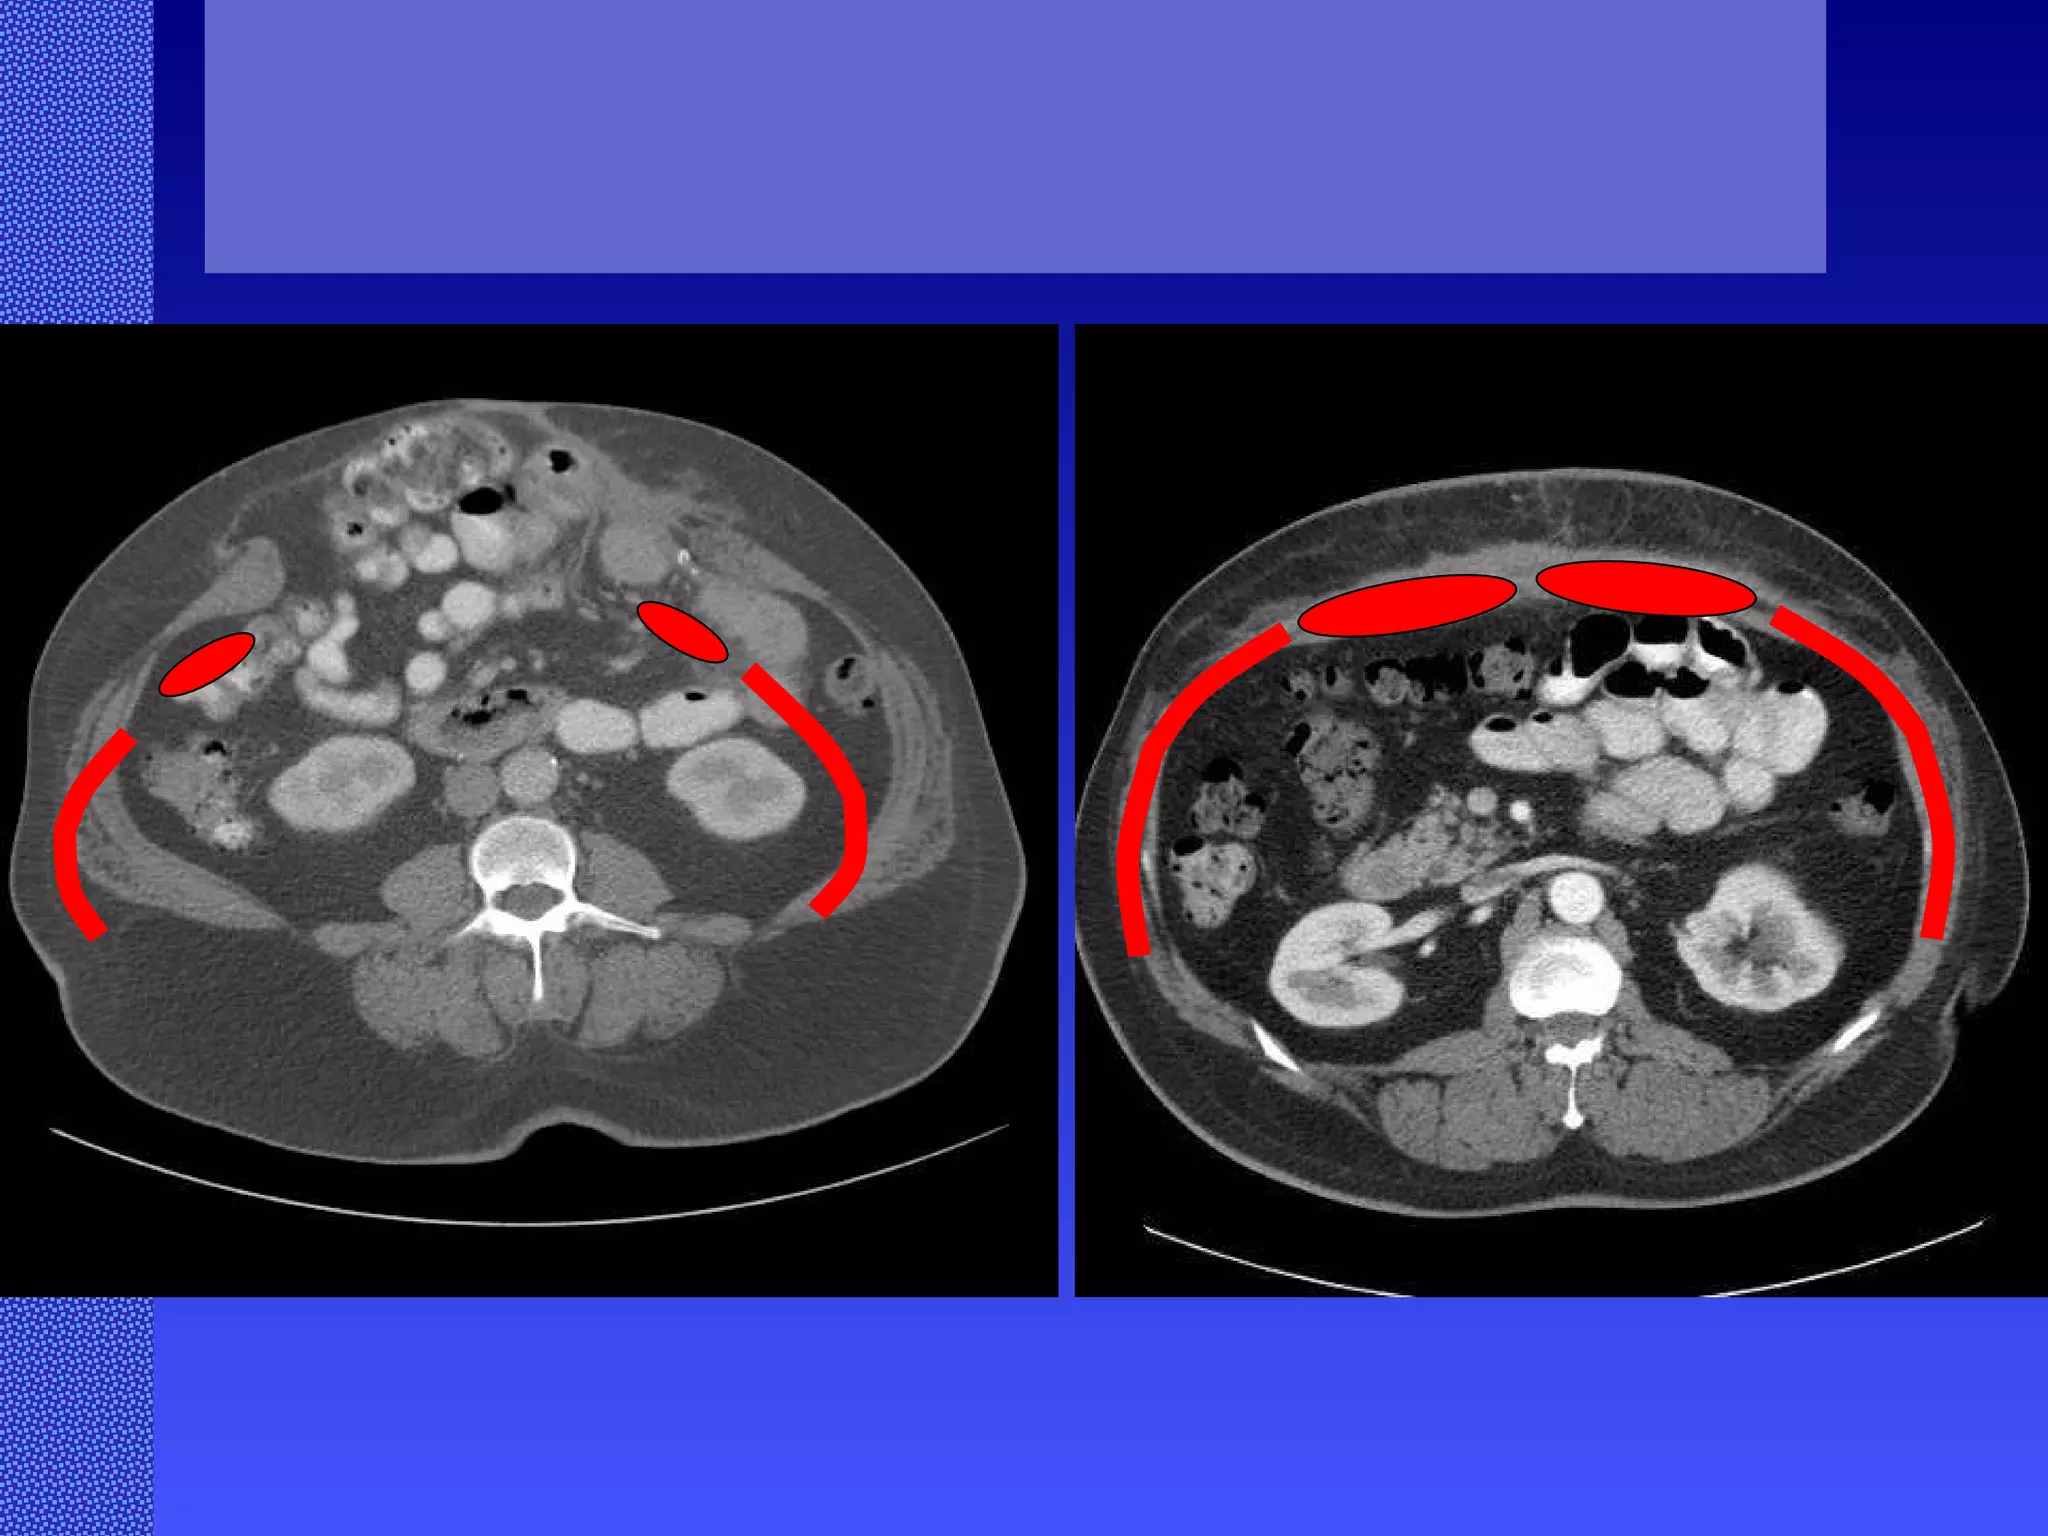

Abdominal Wall Reconstruction: Lessons Learned From 200 “Components Separation” Procedures. Ko, J, MD; Wang, E, PhD; Salvay, D, MS; Paul. B, BA; Dumanian, G, MD ArchSurg/vol 144 (No. 11), Nov 2009  www.archsurg.com Figure 3 A 41-year old man with a history of a perforated appendix treated through a midline incision who later developed an incisional hernia. A, Preoperative oblique view after a hernia repair with polypropylene mesh by another surgeon. B, Preoperative computed tomography scan demonstrating the small bowel herniating to the right of the polypropylene mesh, with wide displacement of the rectus abdominus muscles. C, Six-month postoperative oblique view demonstrates restoration of abdominal wall continuity. D, Postoperative anterior view demonstates stable midline closure and bilateral transverse subcostal incision scars.